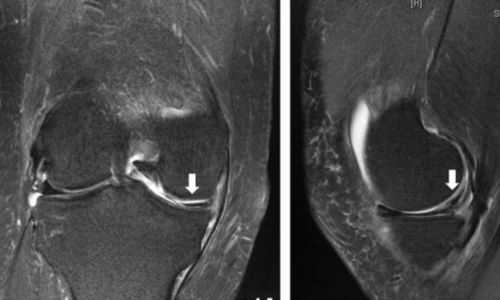

Η διάγνωση γίνεται κλινικά μετά από τις κλινικές δοκιμασίες του ορθοπεδικού (π.χ. test Mcmurray) και η τελική επιβεβαίωση γίνεται μετά από απεικονιστικό έλεγχο με μαγνητική τομογραφία γόνατος.

Η ρήξη μπορεί να αφορά είτε τον έσω μηνίσκο (συχνότερα σε άτομα μεγαλύτερης ηλικίας) είτε τον έξω μηνίσκο (συνήθως η ρήξη αυτή συνυπάρχει με ρήξη πρόσθιου χιαστού συνδέσμου).

Η θεραπεία είναι είτε χειρουργική (αρθοσκοπική συρραφή μηνίσκου ή αρθοσκοπική μηνισκεκτομή) είτε συντηρητική αντιμετώπιση. Η απόφαση για το είδος της θεραπείας γίνεται πάντα μετά από συζήτηση και λεπτομερή ανάλυση του ορθοπεδικού ιατρού με τον ίδιο τον ασθενή λαμβάνοντας υπ' όψιν παράγοντες όπως η ηλικία του ασθενούς, το είδος της ρήξης, τα συμπτώματα που οδήγησαν τον ασθενή να ζητήσει βοήθεια καθώς και το επίπεδο αθλητικής δραστηριότητας του ασθενούς.